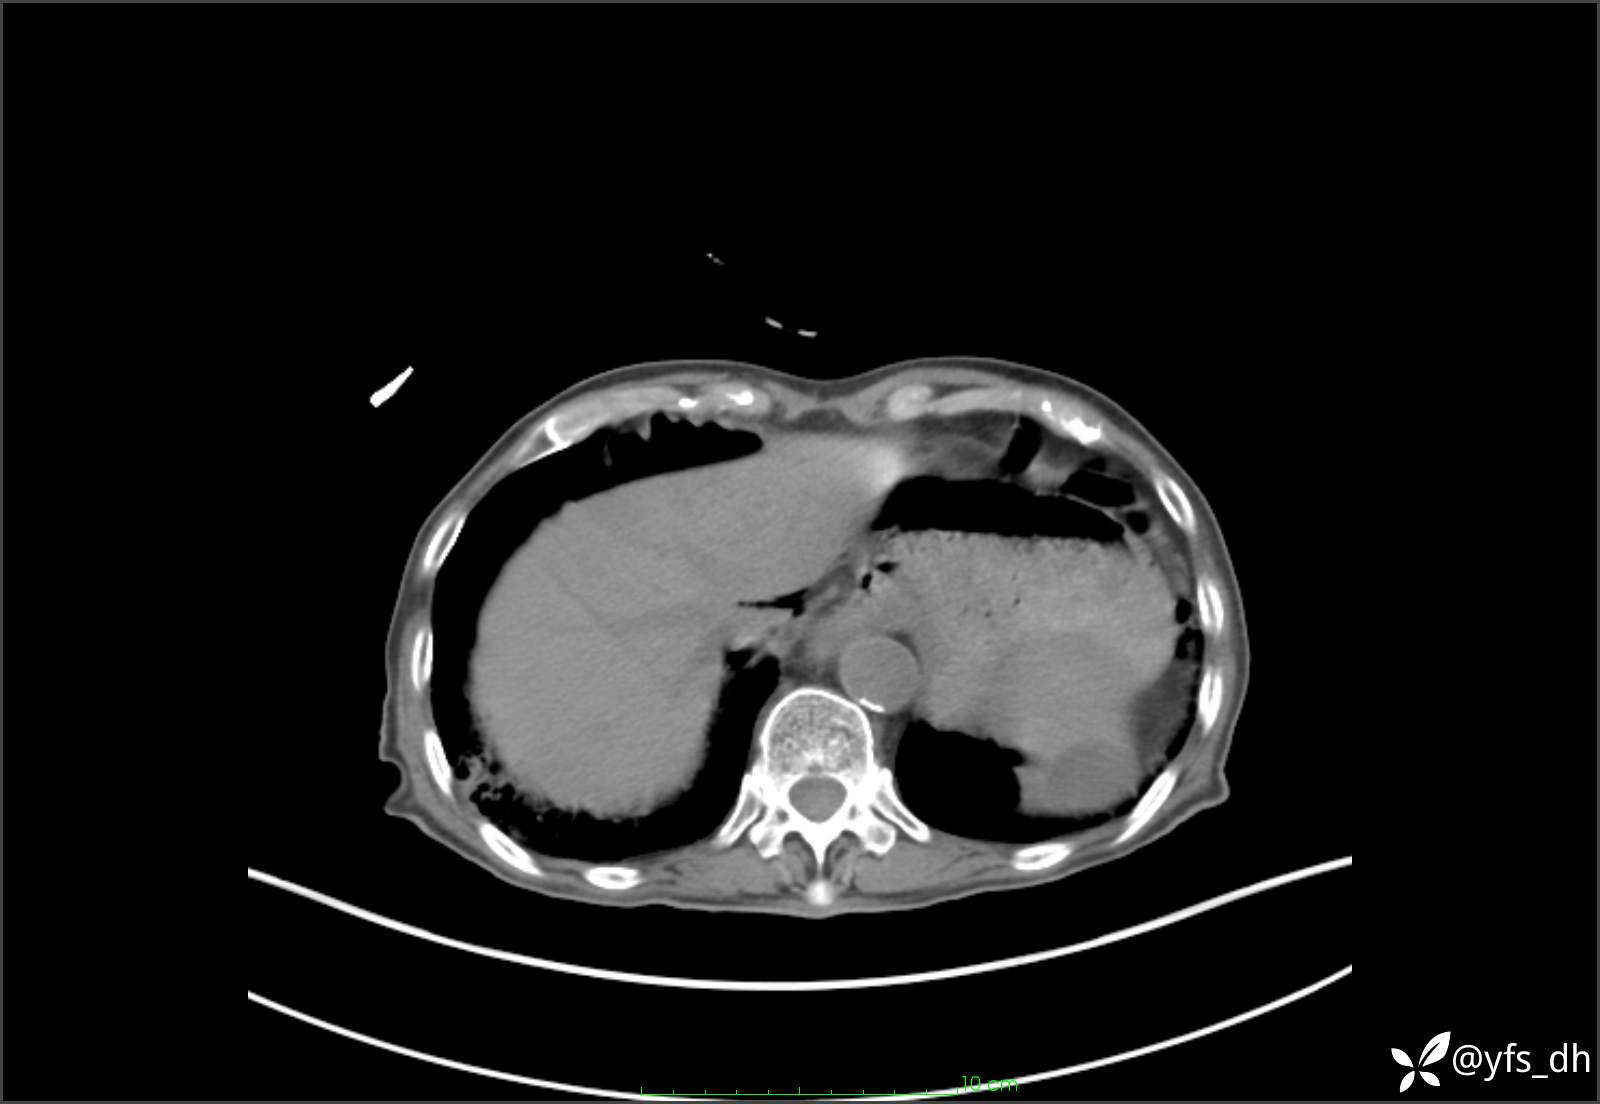

1.简要病史:患者4天前突发上腹部疼痛不适,但可以忍受。3小时前饭后突然加重,不能忍受后就诊。

2.简要手术记录:术中见腹盆腔大量肠液及粪便,乙状结肠中下段见一约3cm的破口。